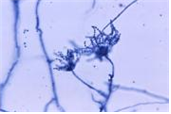

(진균) Talaromyces marneffei

http://phil.cdc.gov/phil/details.asp ID#4192, CDC/ Dr. Lucille K. George; Dr. Arthur DiSalvo

• 특 성 :Trichocomaceae과, 두형태 진균(Dimorphic fungi), 동남아시아에 분포함.(주로 태국과 남중국의 HIV 감염자에서 발생)